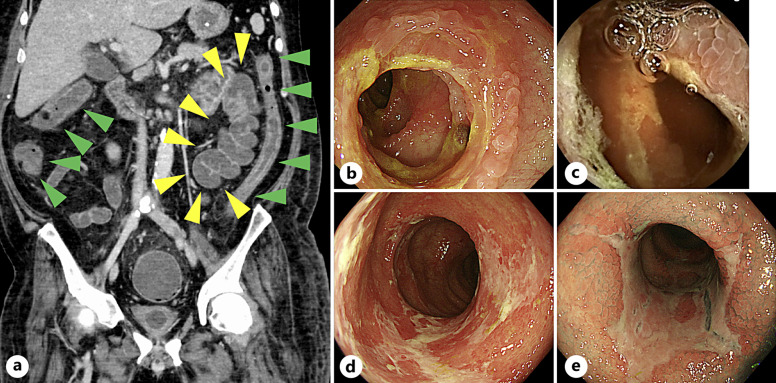

Case presentation: A 50-year-old man with no comorbidities was admitted to our hospital with SARS-CoV-2 pneumonia. His respiratory status deteriorated, and ventilatory management, including extracorporeal membrane oxygenation, was needed. The patient's respiratory condition improved, resulting in a transfer to another hospital for rehabilitation. However, the patient developed diarrhea that worsened to 6,000-7,000 mL/day, and he was transferred to our hospital. We diagnosed the patient with enterocolitis caused by cytomegalovirus infection and treated him with ganciclovir on day 5 after transfer to our hospital. The diarrhea did not improve. We suspected enterocolitis associated with COVID-19 and administered a methylprednisolone pulse (intravenous injection, 1,000 mg/day for 3 days) on day 10 after transfer, resulting in a marked improvement in his symptoms. The prednisolone dose was tapered, and no recurrence of diarrhea was observed thereafter.